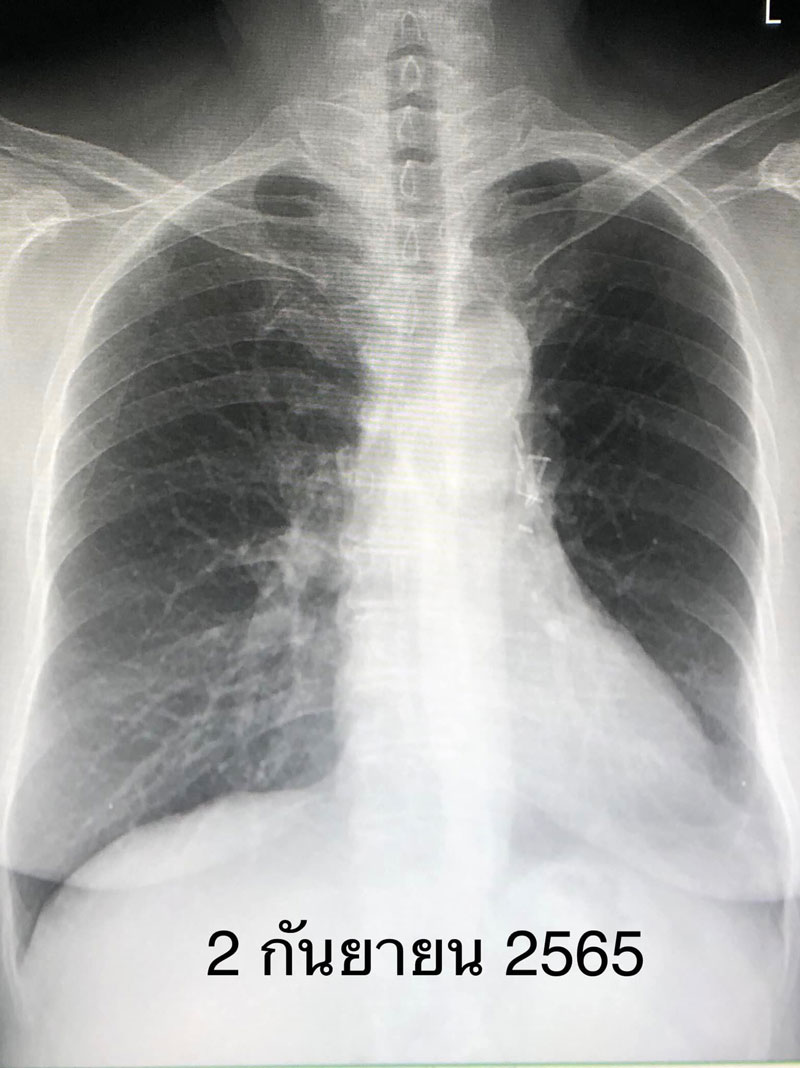

ผู้ป่วยหญิงอายุ 65 ปี เมื่อ 7 ปีก่อน ตรวจร่างกายประจำปี และเอกซเรย์ปอดทุกปี พบก้อนเล็กๆที่ปอดข้างซ้ายด้านบน ผ่านไป 1 ปีก้อนนี้โตขึ้น (ดูรูป) จึงมาปรึกษา ผู้ป่วยไม่มีอาการ ไม่ไอ ไม่มีไข้ ไม่เหนื่อย ไม่เจ็บหน้าอก น้ำหนักไม่ลด เป็นโรคความดันโลหิตสูง ไม่สูบบุหรี่

แต่จุดธูป 20 ดอกในที่ทำงานทุกวันพฤหัสต่อเนื่อง 6 ปี ทำคอมพิวเตอร์สแกนปอดพบก้อนที่ปอดข้างซ้ายด้านบน ค่ามะเร็งในเลือดปกติ ทำ PET scan สงสัยเนื้องอกเป็นมะเร็งปอด ไม่กระจายไปอวัยวะอื่น ส่องกล้องเข้าไปดูในหลอดลม ไม่พบอะไรผิดปกติ

ได้ทำการผ่าตัดปอดโดยวิธีส่องกล้องเมื่อวันที่ 7 มีนาคม 2558 ตัดปอดกลีบบนข้างซ้ายออก และตัดชิ้นเนื้อจากต่อมน้ำเหลืองที่ขั้วปอด และรอบๆเนื้องอก ผลพยาธิวิทยาเป็นมะเร็งปอดขนาด 4 เซนติเมตร ชนิด adenocarcinoma ยังไม่กระจายเข้าต่อมน้ำเหลือง

สรุป: ผู้ป่วยรายนี้ไม่มีอาการ ไม่เคยสูบบุหรี่ แต่หายใจควันธูปต่อเนื่อง เป็นมะเร็งปอดระยะ 2A ( มะเร็งปอดระยะ 2A คือมะเร็งขนาด 4-5 เซนติเมตร และไม่แพร่กระจายเข้าต่อมน้ำเหลือง หลังผ่าตัดมีโอกาสรอดชีวิตที่ 5 ปี ร้อยละ 60 ) ติดตามผู้ป่วย 7 ปีหลังผ่าตัด ไม่พบมะเร็งปอดกลับมาใหม่ ถือว่าหายขาดจากโรคนี้ (ดูรูป) ผู้ป่วยได้เลิกจุดธูปหลังผ่าตัดปอด”.-008